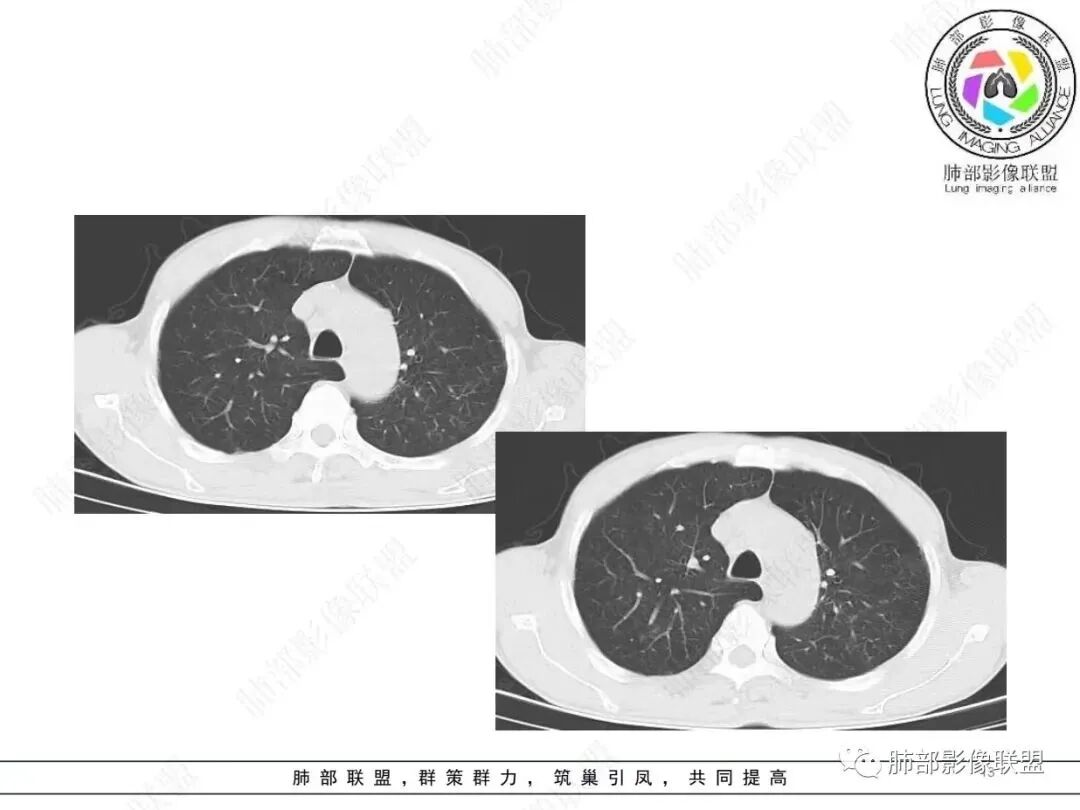

肺部联盟病例男性67岁,咳嗽咳痰两年加重10天。左肺大结节病灶,边缘有切面,以胸膜下粘连,边界柔软,代表良性的病变。病灶的内部有反晕,边缘有少许的抹玻璃样改变,近端有支气管的半进入,周围有支气管的播散病灶。考虑良性病变,结核的可能性大,鉴别诊断就是隐球菌感染。

左肺下叶结节,反晕,边缘平直,边界不清,卫星灶,考虑结核

慢性病史,急性起病,炎性标志物升高,左肺胸膜下结块,边界似清非清,可见晕中软毛刺,邻近肺野见斑点状卫星灶,可见近端支气管充气征,引流支气管管壁增厚,结块局部边缘平直,可见反晕征,综和分析考虑炎性肉芽肿性病变,尽管隐球夾膜试验阴性,但影像上还是首选隐球或TB,其次粘液腺癌

有播散,引流支气管壁增厚,反晕,是要想到TB

3.影像表现双肺可见多发斑片状,条索及结节状高密度影,界不清,树芽征(+),考虑肺结核问题不大。左肺下叶背段结节病灶相对另类,应当警惕结核伴肿瘤,如腺癌。该病灶边缘有刀切征,未见典型分叶毛刺,结合周围有卫星灶,胸膜增厚粘连,可疑反晕,边缘有少许的磨玻璃样改变、较模糊,病灶周围有条索、树芽,相对强化较轻微,一元论考虑肺结核可能性大。腺癌如伴有磨玻璃多为中心实性成分周围为磨玻璃成分,且病灶膨隆为主、可见分叶、毛刺、胸膜凹陷、血管集束,脐凹征等征象,本例有轻微胸膜长线牵拉凹陷但其余肺癌常见恶性征象均不明显,且出现边缘平直等明显指向良性病变的征象。

左肺下叶片状影,边界不清,强化明显,更符合感染性炎性病变。